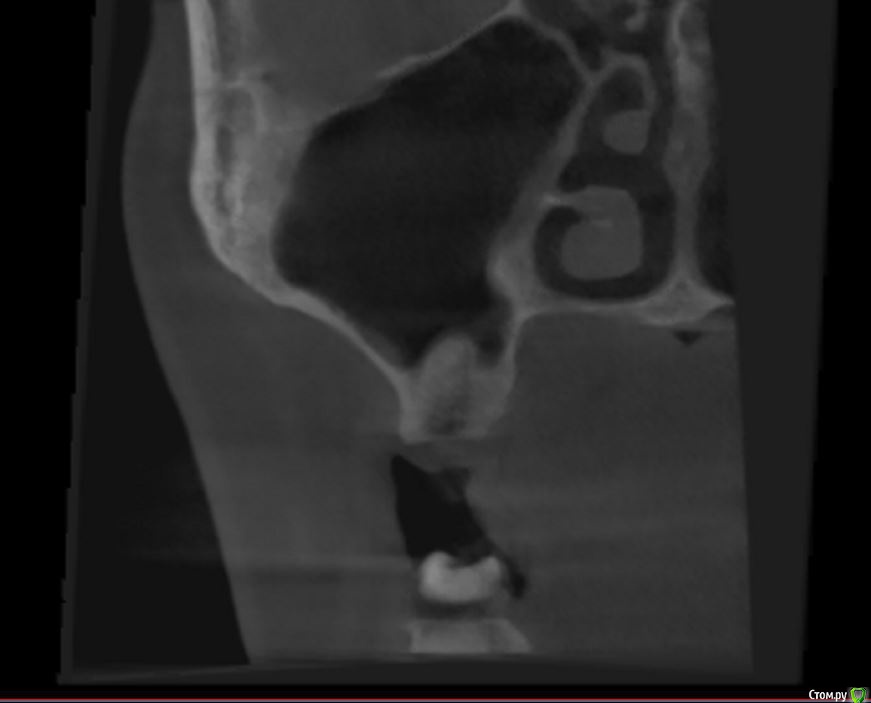

jm3300 Опубликовано 14 июля, 2016 Автор Поделиться Опубликовано 14 июля, 2016 выкладываю кт Ссылка на комментарий

умножающий печаль Опубликовано 14 июля, 2016 Поделиться Опубликовано 14 июля, 2016 Промыть пазуху через соустье, курсом. Я отправляю к ЛОРам. Антибиотикотерапия, гипосенсибилизация. Один из винтов вестибулярно без костной поддержки, на мой взгляд. 1 Ссылка на комментарий

jm3300 Опубликовано 14 июля, 2016 Автор Поделиться Опубликовано 14 июля, 2016 Промыть пазуху через соустье, курсом. Я отправляю к ЛОРам. Антибиотикотерапия, гипосенсибилизация. Один из винтов вестибулярно без костной поддержки, на мой взгляд. гайморит всё таки есть? 1 Ссылка на комментарий

syrovovec Опубликовано 15 июля, 2016 Поделиться Опубликовано 15 июля, 2016 (изменено) Пазуха чистая, Антон, какой винт на выход не понял?Может у пац аллергия ? Изменено 15 июля, 2016 пользователем syrovovec 1 Ссылка на комментарий

kladoffka Опубликовано 15 июля, 2016 Поделиться Опубликовано 15 июля, 2016 Тоже не понял, вроде все хорошо стоят. Главное слизистые то в покое. 1 Ссылка на комментарий

умножающий печаль Опубликовано 15 июля, 2016 Поделиться Опубликовано 15 июля, 2016 (изменено) гайморит всё таки есть?Судя по симптоматике, которую вы представили, есть. На снимке признаки могут запаздывать, ежели процесс острый, хотя снижение пневматизации должно быть заметно. Я на мониторе не разглядел. Рентген всего лишь доп. метод обследования. Диагноз ставит врач, то есть вы, сопоставив клинику и доп.методы.З.Ы. Я не думаю, что в вашем случае причина гайморита имплантация. Временной интервал слишком велик. Изменено 15 июля, 2016 пользователем умножающий печаль 1 Ссылка на комментарий